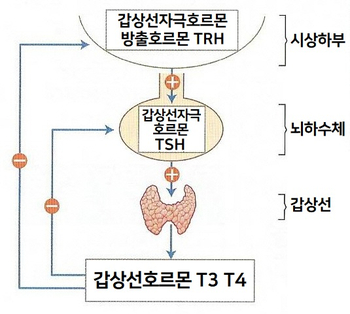

갑상선 호르몬 분비 갑상선 호르몬 분비는 그림과 같이 뇌하수체(TSH), 시상하부(TRH)의 다단계 영향을 받고 있으며 음성 되감기 전에 의해 항진되지 않도록 조절되어 있습니다. 갑상선 기능은 갑상선 호르몬을 생산하는 능력을 말하며, 갑상선 기능 저하증에서는 갑상선 호르몬의 혈중 농도가 낮습니다.갑상선에서 분비되는 갑상선 호르몬의 하루 분비량은 T4(thyroxine)가 80μg으로 가장 많고 T3가 4μg, 비활성형 rT3가 2μg입니다. T4는 간, 신장 등에서 탈요오드화하여 1/3은 T3로, 1/2은 rT3로 전환됩니다.